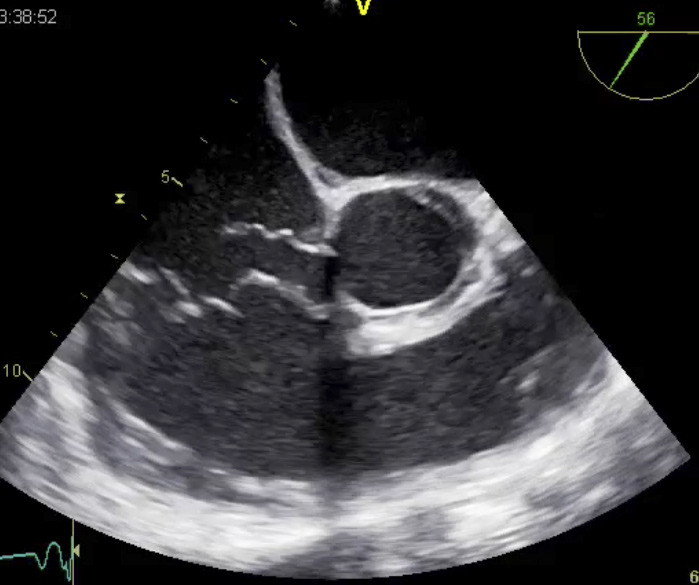

Man påviste Pneumocystis jiroveci ved hjelp av PCR fra trakealsekret. Underliggende immunopati ble ikke påvist, og funnet hadde sannsynligvis ingen klinisk betydning. Etter fem døgn ble det som ledd i en fornyet, bred utredning utført ny ekkokardiografisk undersøkelse. På det tidspunkt var blodtrykket 138/45 mm Hg, og auskultatorisk forelå det systolisk og diastolisk bilyd. Etter transtorakal og transøsofageal ekkoundersøkelse ble det konkludert med at det ikke forelå ventrikkelseptumdefekt, men et rumpert sinus valsalvae-aneurisme med en stor shunt fra aorta til høyre atrium (fig 1, fig 2).

Aortaklaffen var bikuspid, med manglende separasjon av høyre og ikke-koronare kusp. Klaffen åpnet seg godt, og det var kun minimal valvulær lekkasje. Aortaroten var ikke dilatert. Pasienten ble operert, og det rumperte aneurismet ble lukket med suturer både på atrie- og aortasiden. Da ble det rask klinisk bedring, med reversering av nyre-, lever- og respirasjonssvikt. Pasienten ble utskrevet etter nærmere to måneders sykehusopphold i tilnærmet normal form.

Parasternale langakse- og kortaksebilder gir best oversikt over aortaroten, og ruptur kan identifiseres ved hjelp av fargedoppler som et turbulent systolisk og diastolisk shuntsignal fra aorta til mottakende kammer. Ved ventrikkelseptumdefekter ses vanligvis kun shunt i systole. Alle affiserte hjertekamre kan dilatere som uttrykk for volumbelastning ved et rumpert sinus valsalvae-aneurisme.

Transøsofageal ekkokardiografi gir ofte bedre oversikt over aortaroten enn transtorakal ekkokardiografi og kan være spesielt nyttig for å skille mellom rumpert sinus valsalvae-aneurisme og perimembranøs ventrikkelseptumdefekt. Trykkforskjellen mellom aorta og mottakende kammer i diastolen gir større shunt i diastolen og høyere diastoliske hastigheter enn det man ser ved ventrikkelseptumdefekt. MR-undersøkelse, CT-angiografi eller invasiv aortografi kan benyttes der det er tvil om det foreligger et sinus valsalvae-aneurisme. Denne pasienthistorien viser likevel at diagnosen kan være vanskelig.

En retrospektiv gjennomgang av ultralyd- og MR-bilder fra vår pasient viser at det rumperte sinus valsalvae-aneurismet var synlig også på de første bildene og ble feiltolket som en perimembranøs ventrikkelseptumdefekt. Størrelsen på defekten og følgelig shuntvolumet økte imidlertid betydelig fra innleggelsestidspunktet til operasjonstidspunktet. Dette aktualiserer derfor også behovet for en fungerende teknisk løsning for overføring av ekkokardiografiske bilder mellom lokalsykehus og regionsykehus for konferanse om uvanlige og vanskelige kliniske problemstillinger.